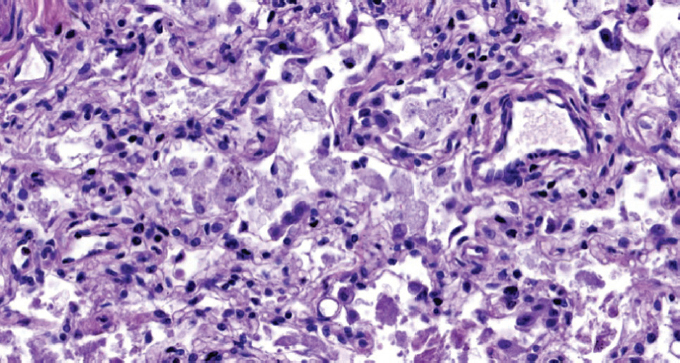

Children get sick less often than adults with a new coronavirus infection (in the Russian Federation, they account for 7.6% of registered cases of COVID-19), with less severe clinical symptoms, they require hospitalization less often, their disease is milder. The frequency of severe and extremely severe cases of COVID-19 in children does not exceed 1%. A clinical case of the course of COVID-19 in a child aged 2 years 4 months is presented. with acute lymphoblastic leukemia. A feature of the presented case is the development of an extremely severe new coronavirus infection in a child with secondary immunodeficiency caused by a long-term course of malignant, treatment-resistant of acute lymphoblastic leukemia. Slow, within 3 months, the development of the infectious process with long-term preservation of normal indicators of the function of the respiratory system led to the formation of viral-bacterial pneumonia with the development of respiratory distress syndrome. Despite the modern complex of therapeutic measures, severe comorbidity led to the development of DIC and multiple organ failure, which was the direct cause of the child’s death. A possible therapy strategy is discussed in a patient with severe comorbidity against the background of secondary immunodeficiency and long-term persistence of SARS-CoV-2 in the presence of IgG antibodies to SARS-CoV-2 in the blood. For the first time, data on morphological changes in the lungs with a long course of COVID-19 (more than 100 days) in a young child are presented.